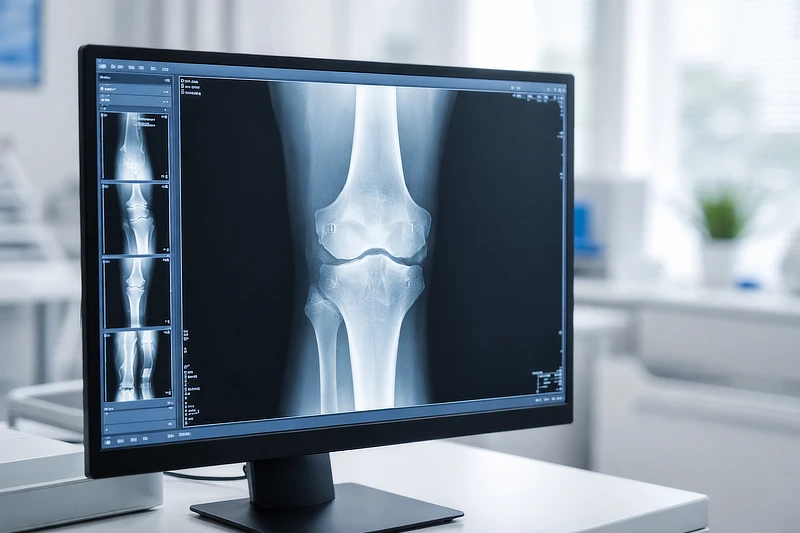

A pesar del avance de las técnicas de imagen, la radiografía simple continúa siendo, hoy en día, una herramienta esencial en el diagnóstico inicial de los tumores musculoesqueléticos. Su accesibilidad, rapidez y capacidad para identificar signos radiológicos de alarma la convierten en la primera prueba de referencia para orientar la sospecha de lesiones potencialmente malignas.

La combinación de una exploración clínica detallada y una radiografía simple permite, en la mayoría de los casos, descartar patología tumoral o identificar signos radiológicos de alarma.

La radiografía simple sigue siendo la primera prueba clave para orientar el diagnóstico inicial de los tumores musculoesqueléticos.

Aunque poco frecuentes, los tumores musculoesqueléticos deben tenerse en cuenta en la práctica clínica diaria. La radiografía simple sigue siendo una herramienta fundamental para la orientación diagnóstica inicial, y la traumatología desempeña un papel clave como primera línea de detección.